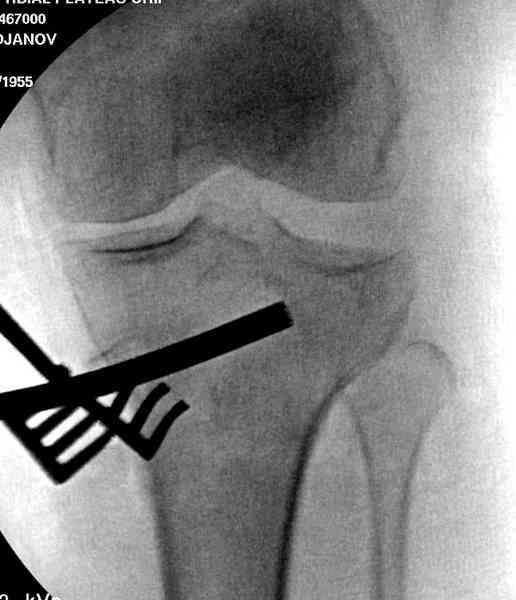

Нет, малоберцовый внизу, фиксацию проводим на верхнем эпифизе, где твердая кость. Задача состоит

в том, чтобы создать арматуру из нескольких проведенных шурупов на эпифизе.

Медиально, обычно на протовоположной

строне, делается окно в кортикальном слое, кривым забойником под рентгеном поднимается импрессия.

Это техника применяется, когда имеется

центральная импрессия, а при ипрессии с краевым переломом - после приподнимания импрессии опорная (Butress) пластина, как на снимке.